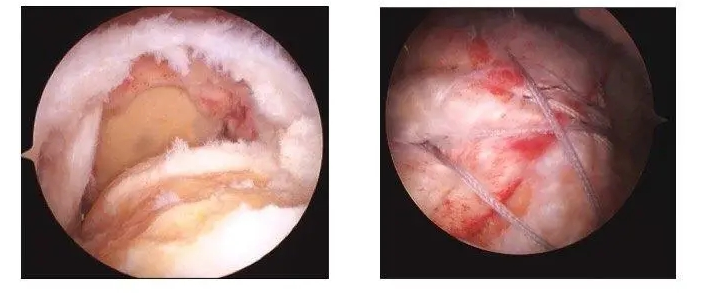

镜下图片

案例:患者吴某,女,62岁,因右肩部疼痛、活动受限3个月入院治疗。MRI示:右肩袖损伤,冈上肌肌腱断裂,右肩关节退行性改变。入院后完善相关辅助检查,在全麻下+臂丛麻醉下行右肩关节镜下肩袖修补术,患者术后肩部疼痛明显缓解,手术切口小、恢复快,指导患者功能锻炼,术后第三天康复出院,患者对治疗效果很满意。

肩袖损伤是临床上常见的疾病,是指肩关节周围组织,即冈上肌、冈下肌、小圆肌以及肩胛肌损伤,临床主要以疼痛为主,特别是侧卧时,疼痛感严重加剧,可引起患者功能障碍,影响患者生活质量。肩袖损伤疾病主要好发于中老年群体或者是长期从事体力劳动者,出现此病的原因是由于肩关节组织发生结构磨损,引起此病最主要的因素的是肩关节撞击综合征,且冈上肌损伤是此病常见的表现。肩袖损伤具较高的发病率,且误诊率偏高,临床表现夜间疼痛、伴随肩部乏力、肌力减弱等,且患者运动时同样会伴随强烈剧痛感。随着微创技术的发展以及进步,选择肩关节镜手术治疗此病效果良好,具有创伤小、疼痛感较低、术中出血量少、术后并发症少、肩关节恢复速度快等优势。武宁县人民医院骨科已顺利开展关节镜下肩袖修补术,且取得较好效果,患者住院周期为5-7天,创伤小、疼痛感较低、恢复快。